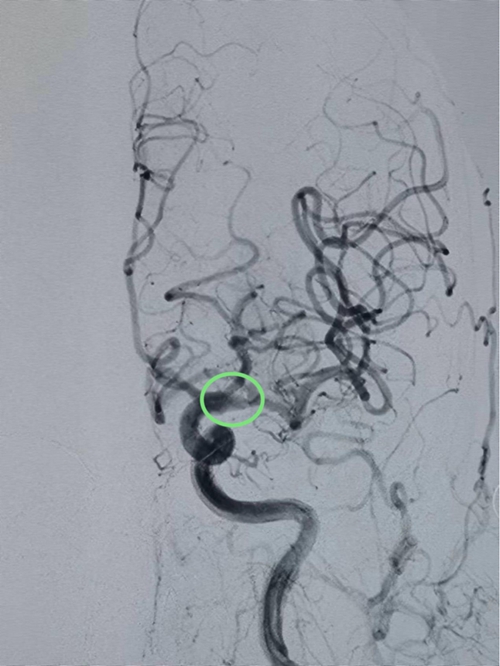

△抽吸1次血管实现再通

李华军教授带领团队凭借精湛娴熟的技艺,用抽吸导管抽出数块血栓。复查造影显示患者左侧颈内动脉远端闭塞处已开放,左侧大脑前动脉、左侧大脑中动脉及各分支显影良好,前向血流达mTICI 3级——一次性取栓成功!

从穿刺到血管再通仅用时40分钟,远少于指南上的目标值60分钟!